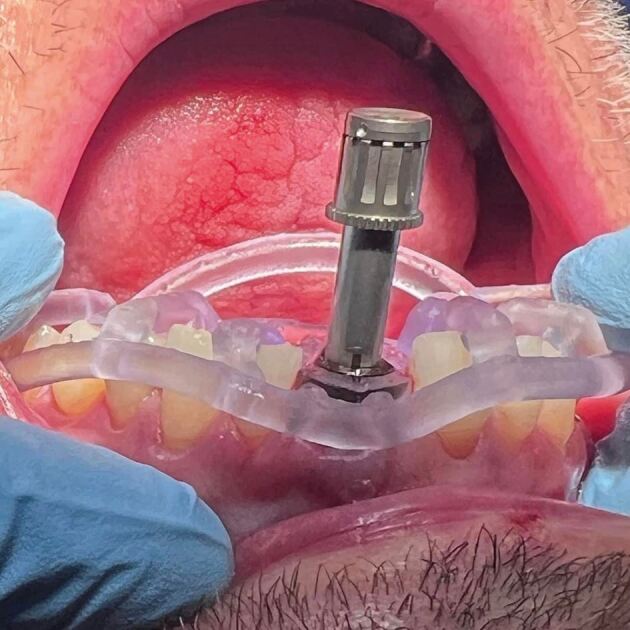

The accuracy variation between these guides is the guide's stability on the soft tissues, teeth and bone (Fig. 1).

Fig. 1.

Dentate-guided implant surgery